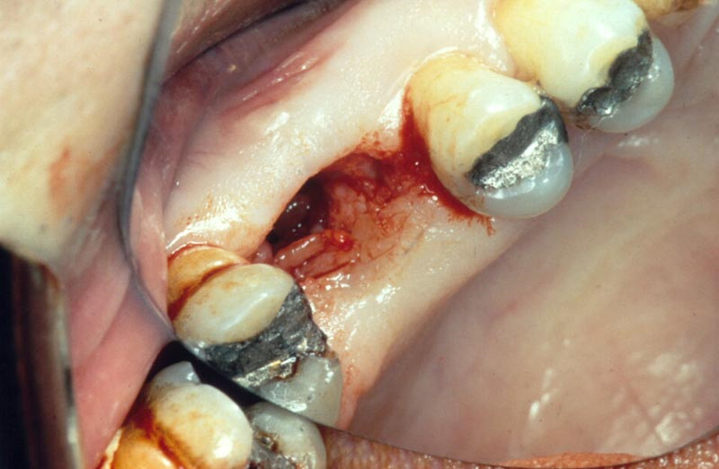

Q

What is this image showing?

A

• Acute Oro-antral communication